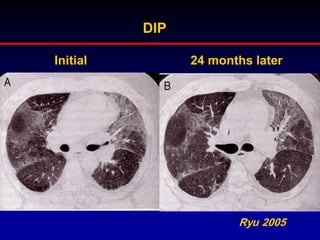

DIP

Initial

24 months later

Ryu 2005

Controversies with RBILD/DIP

• Should RBILD be included in the IIP„s?

100% are cigarette smokers, so a

disease of known aetiology!

• DIP is not exclusively seen in smokers,

15% are nonsmokers

Ryu et al. Chest 2005,127:178